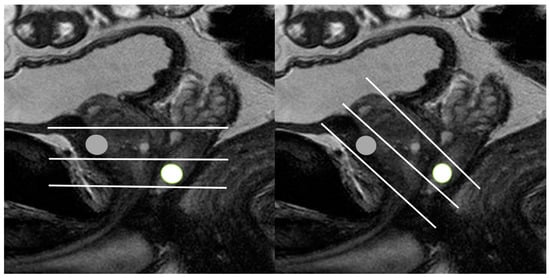

| Tumor Location/Morphology | MRI | TRUS |

|---|---|---|

| Scan axis to urethra | Perpendicular | Oblique |

| Anterior 1/3 location | Base and mid-gland | Mid-gland and apex |

| Middle 1/3 location | Same location | Same location |

| Posterior 1/3 location | Apex and mid-gland | Mid-gland and base |

| Tumor size | Different size | Different size |

| Tumor shape | Different shape | Different shape |